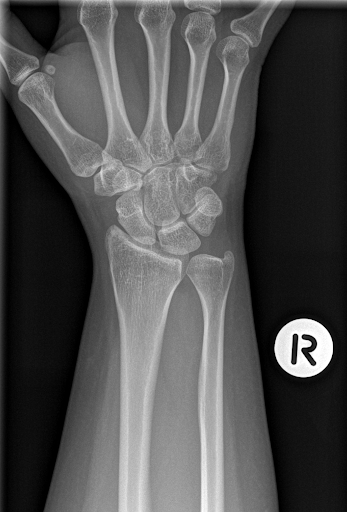

65 year old woman who presents to the ED with diffuse right wrist pain after a FOOSH while chasing her dog. On exam you note tenderness on the radial aspect of the wrist, including localized tenderness of the anatomic snuffbox. Her XR is below. What is your treatment plan?

Answer is D. This patient had a FOOSH (fall on outstretched hand) with an exam concerning for an occult scaphoid fracture despite a normal XR as shown. Up to 10% of initial x-rays in patients with scaphoid fractures are normal. Given the high risk of morbidity related to an undiagnosed scaphoid fracture - avascular necrosis leading to chronic functional impairment and pain - it is important to treat the patient for a scaphoid fracture if your clinical suspicion is high. This includes placing a thumb spica splint and arranging close follow up with orthopedics and repeat imaging outpatient.